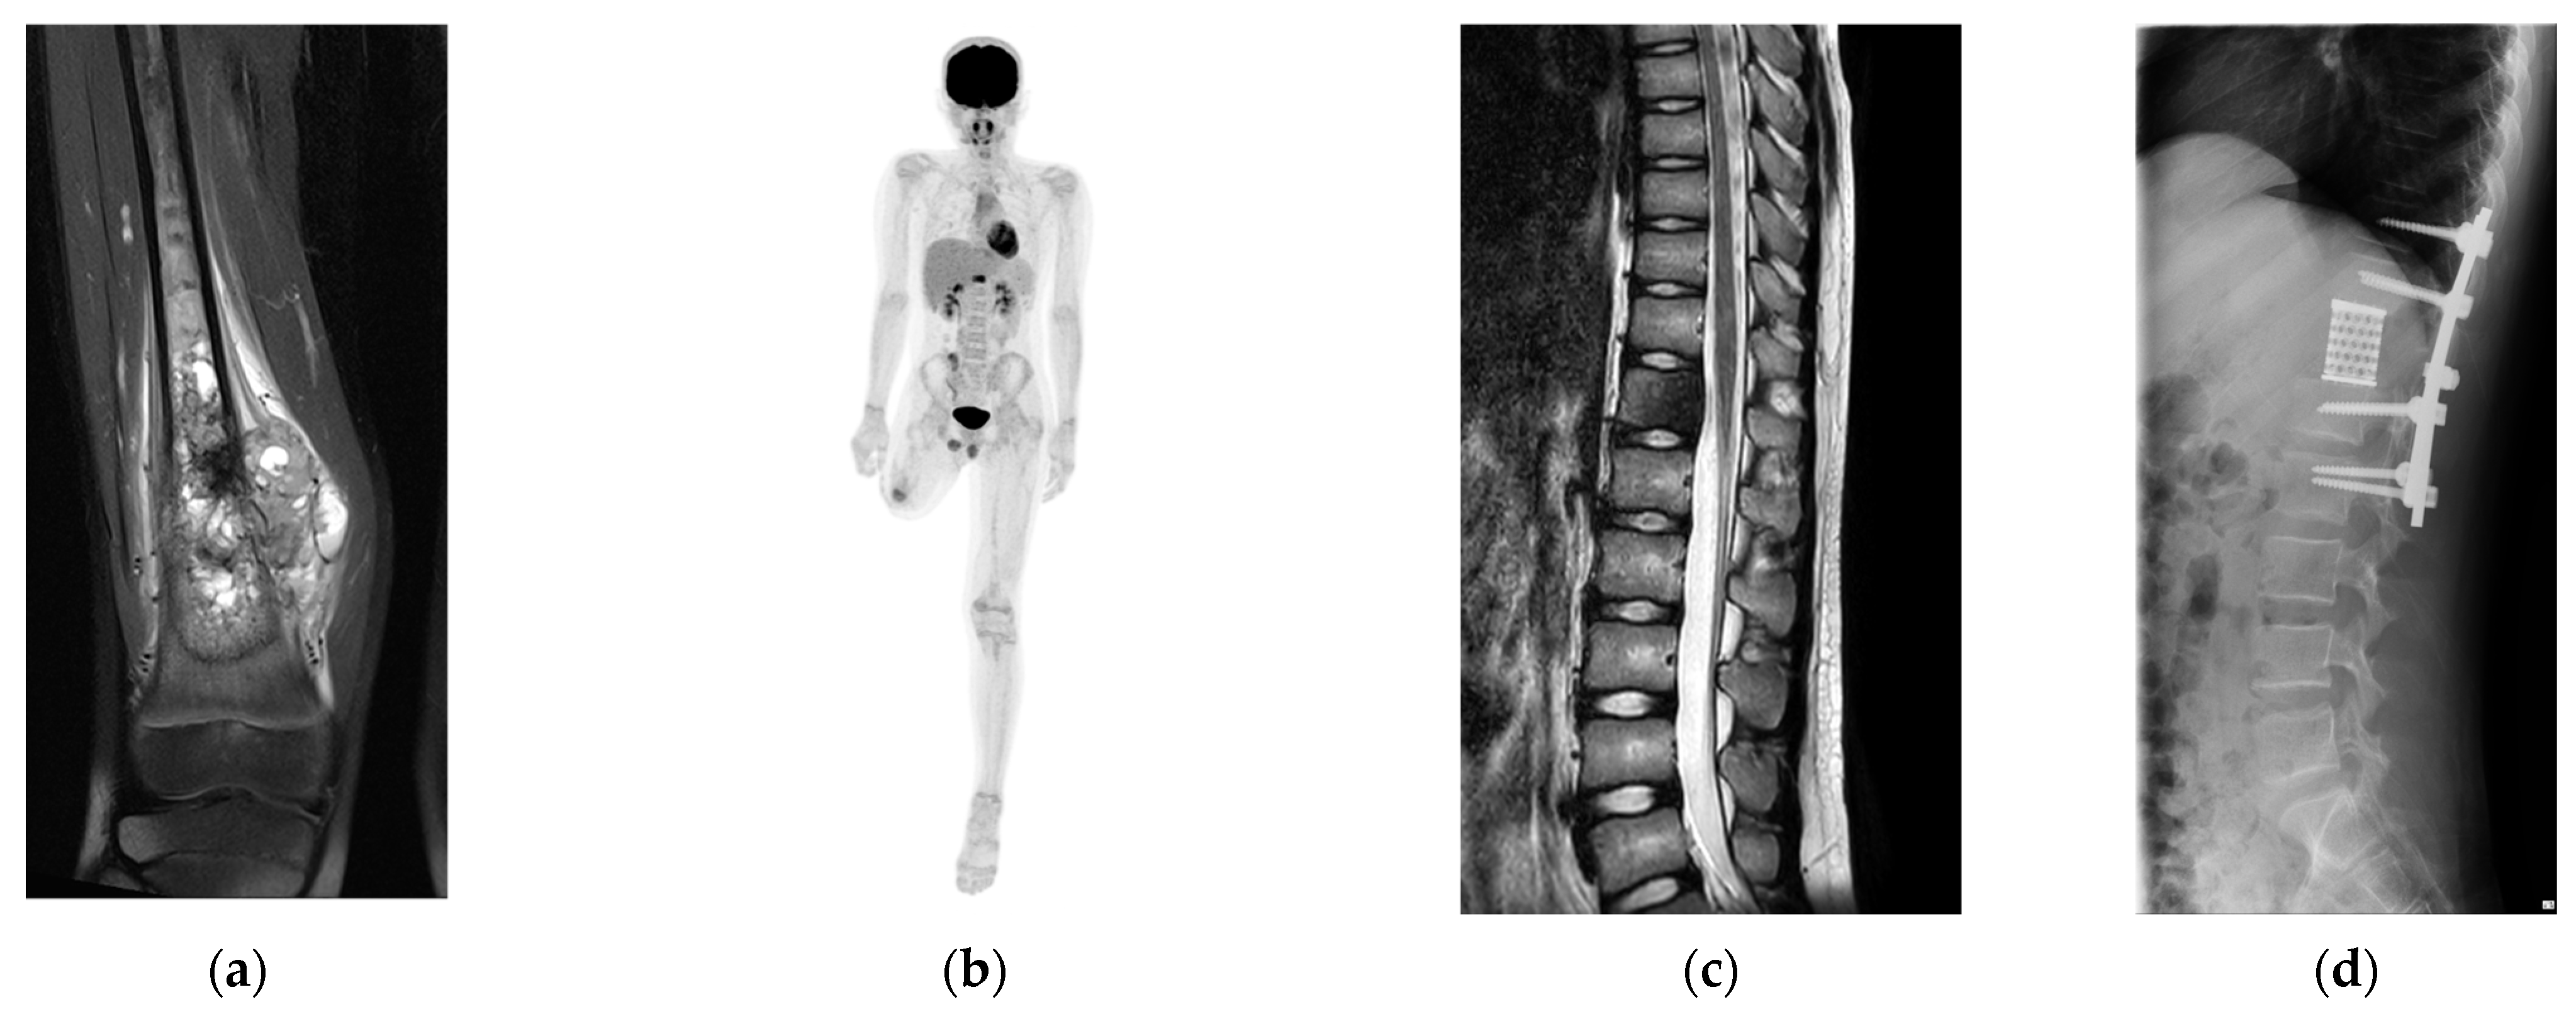

2.1. Patient

2.2. Tumor Resection and Reconstruction